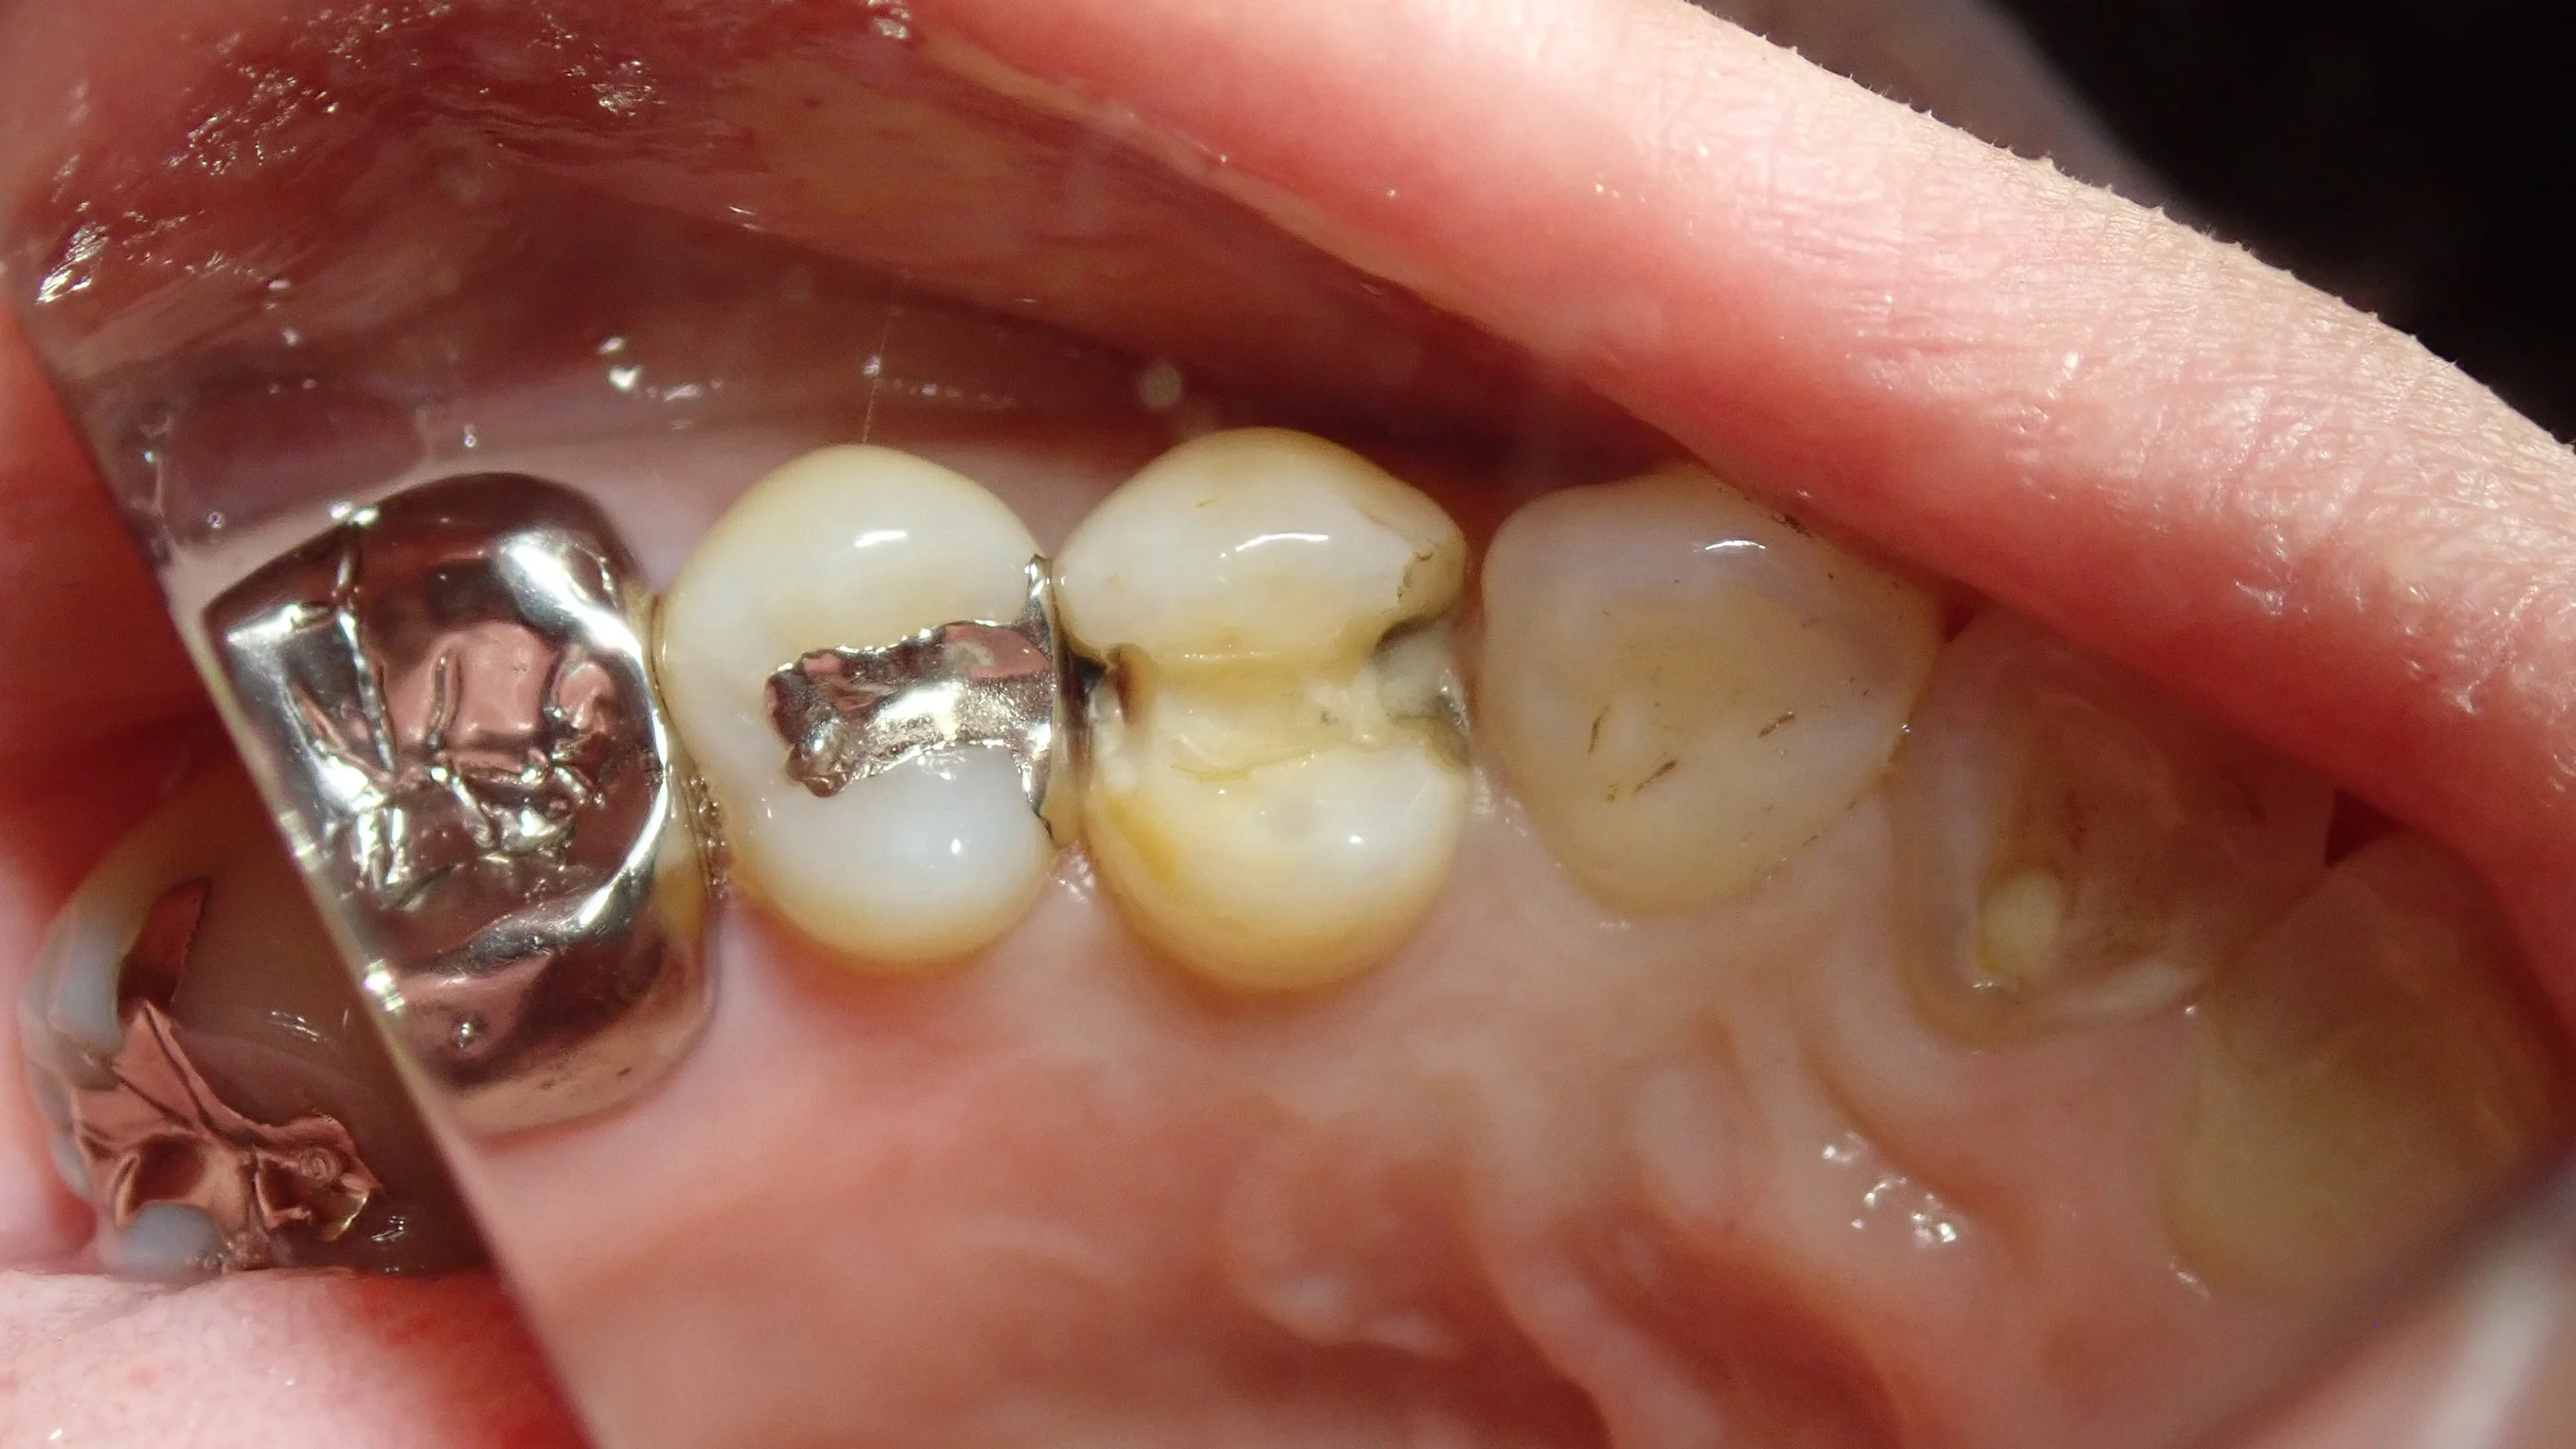

で、術前の写真がこちらです。

画面真ん中にある、両隣の歯に延びている金属の詰め物が入っている歯が今回治療した歯です。

ある程度経験を積んだ歯科医師であれば、このインレーを見た瞬間に・・・

「おぉぅ・・・虫歯になりやすい形態だなぁ・・・」

って思うと思います。